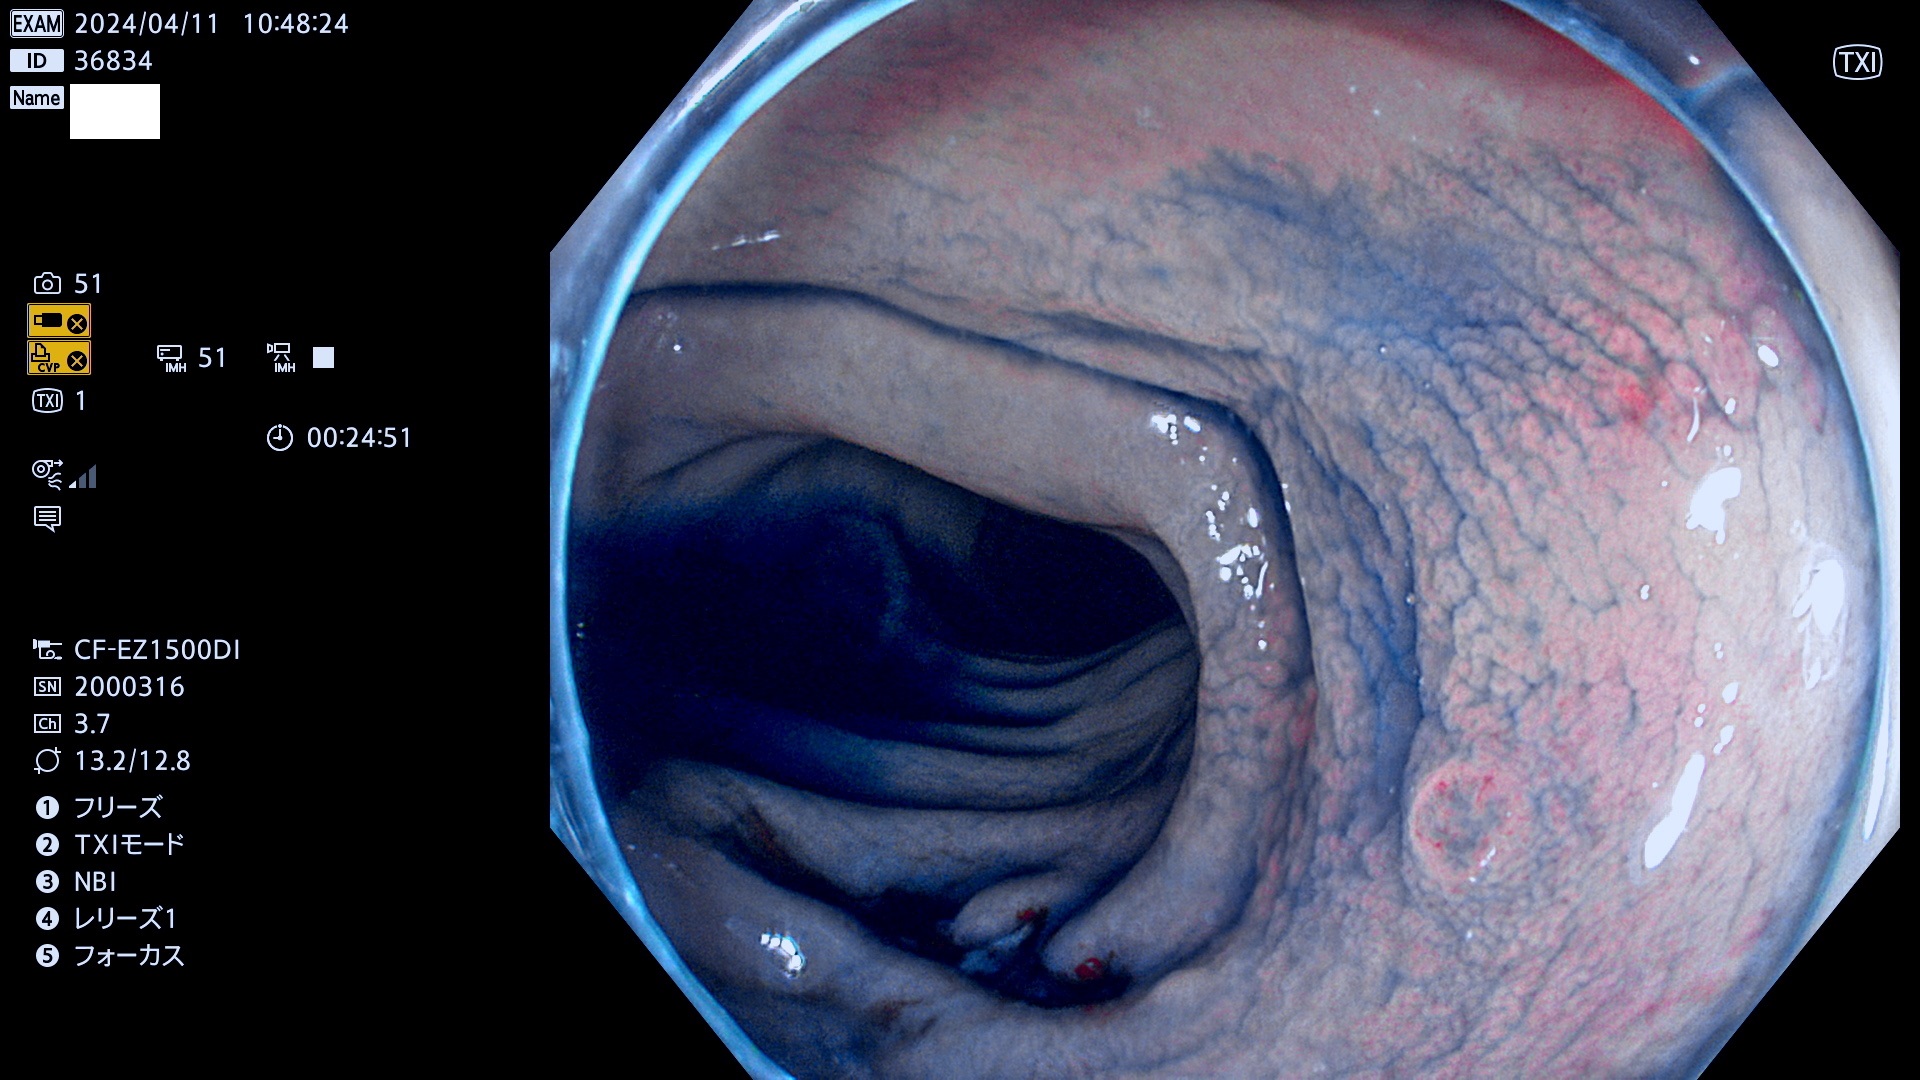

今週のUb、Uc型腺腫

表面型腺腫(Flat Adenoma)の中で、完全に平坦な物をUb、陥凹している物をUcと呼びます。平坦隆起型(Ua)よりも、発見が難しく危険な病変です。

専門的)Uc=De Novo癌? 内視鏡の解像度が低かった時代、このような説もありました。しかし今日の高精度内視鏡では良性の微小なUc型腺腫が日常的に見つかります。私見ですが「Ucこそが多段階発癌(Adenoma-Carcinoma Sequence)のMain Route」と考えます。

毎週の検査(木・金・土・日)に発見されたUb、Uc型・腺腫を、その週の日曜の夜にUPし1週間、提示します。

抽出の対象期間 2024年4月11日〜4月14の4日間(40件の検査)3件 (3/40=8%)